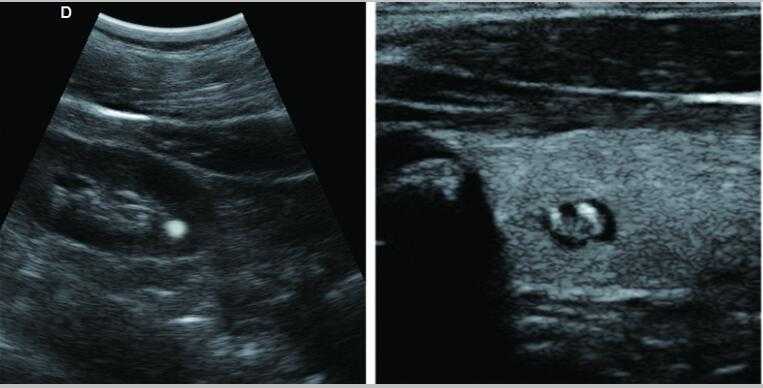

牛羊馬豬犬貓及多種家禽、實驗動物、野生動物、及部分水生動物

L3-VET便攜筆記本式獸用B超機適用探頭